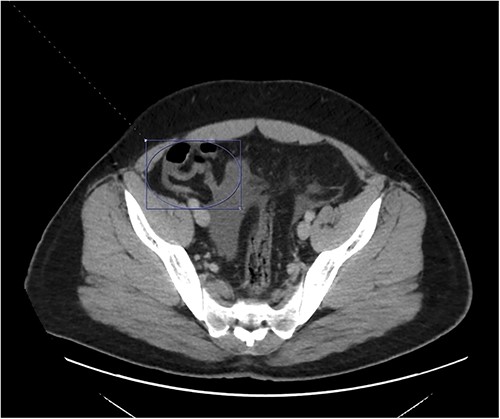

At home, the patient continued to do well and remained free of abdominal pain. He was tolerating a normal diet without emesis and was having normal bowel function. His outpatient CT scan 3 months after discharge demonstrated near resolution of his subocclusive PV and SMV thrombus and attenuated periappendiceal inflammation (Figs 3 and 4). Given the patient’s clinical stability and benign radiographic findings, the patient was scheduled for a laparoscopic appendectomy.

Only a slender portion of thrombus remains in the main portal vein; the previously seen splenic vein thrombosis has largely resolved (not well visualized).